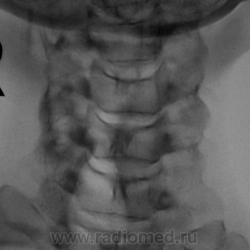

Дополнительные изображения с увеличением.

У данной пациентки - выраженное нарушение статики, а значит смело можно писать дискоз + снижение высоты межпоз. диска в С5-С6 позв. сегменте = остеохондроз.

Андрей Юрьевич

1.Касаемо остеохондроза С5-6 - вне всякого сомнения и...не вчерашний.

2. Кифотическая деформация (она же функциональная установка по Игорю Ивановичу, она же - анталгическая - по Валетнину Львовичу, что, впрочем, одно и то же по сути)-вне всякого сомнения....но она же - предупреждение о клиническом ухудшении; кстати - если придираться, то и кривошея влево, хотть и умеренная, но есть, более чем уверен, что из той же оперы.

3. Касаемо нестабильности в в\шейном отделе, мне кажется - надумано, тем более, что хотим мы или не хотим, целый ряд специалистов указывают на допустимую нормальную подвижность в пределах 0,3 см максимум.

4. Касаемо ретролистеза С6 - вне всякого сомнения, ибо до 0,4 см...если не немного больше.

5. Поход к мануалисту и наличие кифоза, ретролистеза С6, кривошеи, поворота среднешейного отдела вокруг вертикальной оси, хоть и легкого, но имеющегося, приводят к мысли, что имеет место подвывих в одном из дугоотростчастых суставов в пределах С4-С7....вот только вопрос - какого...вот он то и привел к обострению клинической ситуации с остеохондрозом....не вчерашним....